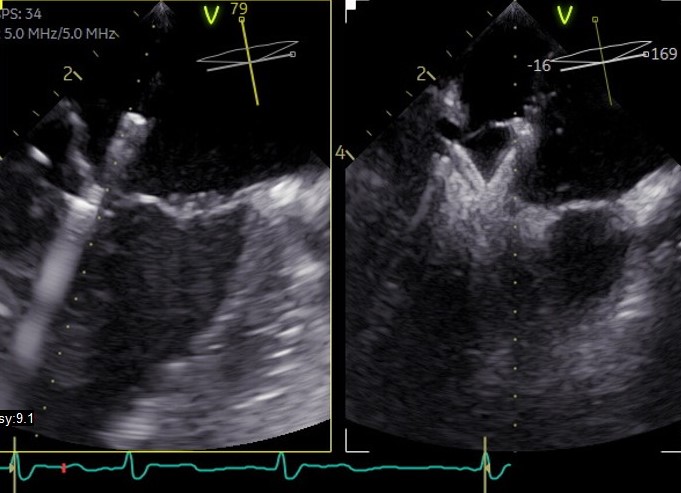

Zur genaueren Untersuchung/Einschätzung der Klappenfunktion sowie -morphologie und Vorbereitung auf die interventionellen Klappeneingriffe („Clipping“) haben wir die Möglichkeit mittels einer transösophagealen Echokardiografie („Schluckultraschall“) 3D-Rekonstruktionen der Herzklappen anzufertigen. Auch kommt dieses Verfahren zum Ausschluss von Blutgerinnseln im Herzen vor der elektrischen Kardioversion oder den Ablationsbehandlungen (Verödung) bei Vorhofflimmern/Vorhofflattern zum Einsatz.

Das Bild illustriert eine durch Schluckultraschall (TEE) gesteuerte Prozedur zur Mitralklappenreparatur (Mitralklappen-Clipping)